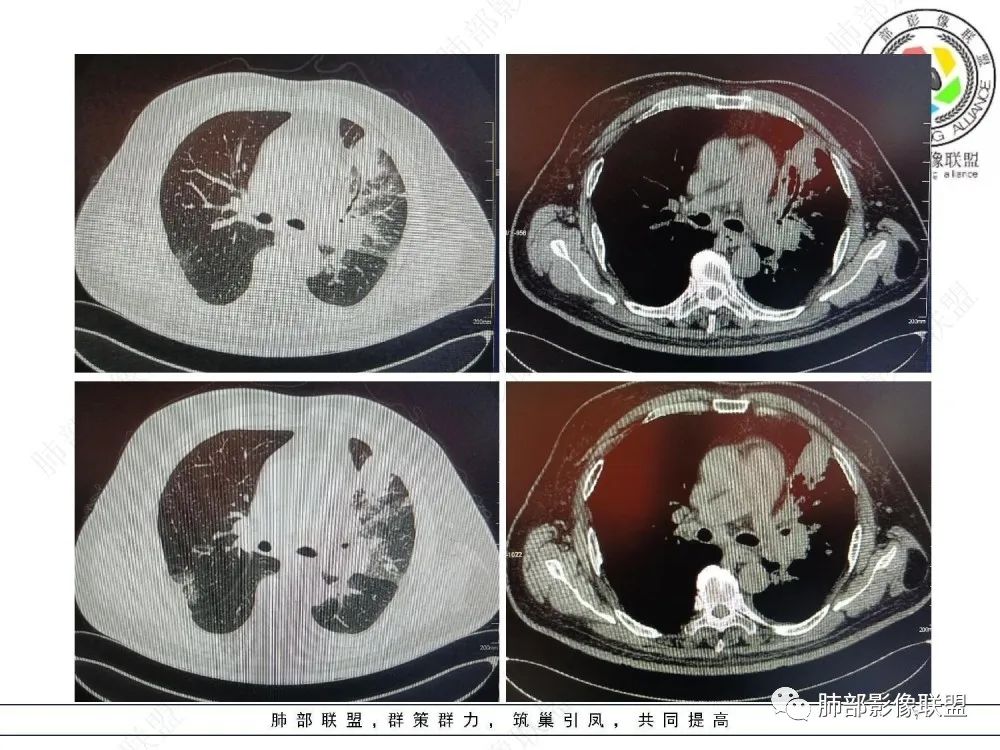

三、影像表现:左肺上叶多发片状高密度影,散在,边缘模糊,支气管壁稍增厚,中轴间质、小叶间隔增厚、有结节感,左肺上叶前段病灶可见胸膜增厚,部分小支气管不能分辨;右肺上叶后段混合磨玻璃结节,边界清,邻近胸膜凹陷;纵膈淋巴结肿大;心包增厚;左侧少量胸水。此外,扫及右侧胸腔内甲状腺肿;左侧肩胛骨旁肌群内脂肪瘤。

四、综合分析:老年男性,以咳嗽咳痰为主要临床表现,无发热,白细胞正常,影像表现为左肺上叶片影,前段结节影、胸膜增厚、部分小支气管不能分辨。左肺上叶中轴间质增厚、小叶间隔增厚、结节感,肺门纵隔见肿大淋巴结,尽管肺部病病灶边缘特征不典型,但高度疑及癌性淋巴管炎这一“次生灾害”却具有相当重要提示意义,而肺癌中最常伴癌淋的就包括腺癌。右肺上叶后段混合磨玻璃结节,边界清楚,张力明显,具有一定特征性,高度指向浸润性腺癌。这对于左肺病灶具有一定程度“助攻”效应。总体而言,本例左肺病灶的诊断关键点在于判断出癌性淋巴管炎。癌性淋巴管炎的结节在外围间质多见,小叶间隔可呈串珠状、结节状增厚,由于出血及水肿,小叶间隔增厚较明显,或呈不规则增厚。有的肺小叶呈多角状阵列。常合并胸水。

肺癌性淋巴管炎(PLC)是肺内、外肿瘤肺转移的一种特殊类型,以 转移癌细胞在淋巴管内弥漫性生长为特征,占肺内转移瘤的6.8%。癌 细胞可播散至肺淋巴管及血管,最终因呼吸衰竭和肺源性心脏病而导致病死亡。临床症状主要为干咳、憋气、体重减轻及低氧血症。本病预后极差,50%~85%的患者生存期3~6个月,临床诊断较困难,常误诊为其它肺间质性病变。 PLC的主要CT征像当中肺纹理异常改变最常见,肺纹理不规则增多、增粗并多发微小结节状更形象解释癌细胞在淋巴管内生长成结节及周围间质增生,导致淋巴管通道堵塞,远处淋巴液回流受阻,通过其它细小交通回流,从而导致肺纹理增粗增多,是PLC较有特征性CT征象,其它疾病所导致的肺纹理增多增粗一般较规则,可为粗细不均或受牵拉变形却极少出现结节状增粗并呈串珠状排列。小叶间隔不规则增厚并多发小结节也是因为小叶间隔淋巴管癌细胞生长及淋巴管通道受阻扩张所致,虽然小叶间隔结节状增粗,但小叶结构不变形是PLC较为特征的CT表现,肺纤维化、 肺水肿、肺胶原病及结节病等肺间质性病变中较少见小叶间隔结节状增粗,而且它们一般导致肺小叶结构变形。肺小叶内间质增生及(或)核心小结节无明显特异性,其表现与特发性肺纤维化、 尘肺及结缔组织病及其它可导致肺间质性纤维化疾病的小叶内间质增厚相类似。PLC导致的胸膜增厚也有一定特征,一般累及胸膜范围较广,程度轻,密度较淡, 部分呈花边样改变,以叶间胸膜较常见,绝大部分病例叶间胸膜受累呈轻度增厚并沿表面排列多发微小结节,伴随PLC其它征象,未见单独存在。肺内结节及 (或)小斑片状实变影无特异性, 与肺结核、炎症、肺血行转移瘤及类风湿等结缔组织病的肺部表现相似,也可能为合并血行转移及肺部感染。纵膈及肺门淋巴结肿大、胸腔及心包积液均无特异性,曾有文献报道,单侧叶间裂积液对PLC的诊断有相对特异性, 因单侧的叶间裂积液主要是由于胸膜下淋巴管堵塞,淋巴回流受 阻所致,可提示PLC的存在。

综合上述,肺纹理不规则增粗并多发微小结节、肺小叶间隔不规则增厚并多发微小结节、轻度增厚的胸膜并多发微小结节对诊断PLC具有重要意义,三者征像同时存在时,结合肿瘤病史及临床症状, 基本可以明确诊断PLC。